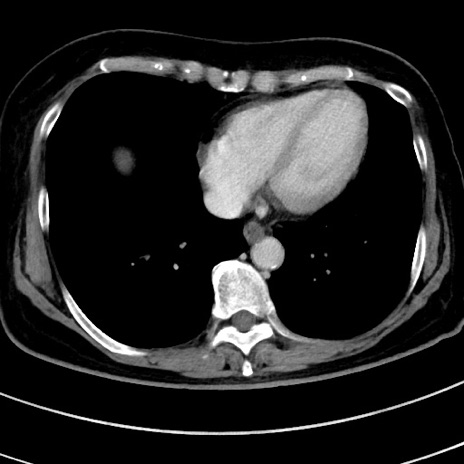

冠状断像

【症例】 60歳代女性

【主訴】むかつき、みぞおちの痛み

【現病歴】3日前よりむかつきがあり、食事がとれない。

【既往歴】糖尿病

【身体所見】発熱なし、心窩部圧痛軽度あるも、腹膜刺激症状なし。

【データ】WBC 7400、CRP 1.92